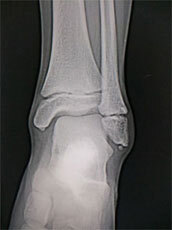

10月は足関節

足関節を痛める場合「ひねる」原因がほとんどですが、今回の9名中、7名がひねっています。状況はさまざまで、体育中、部活中、階段をおりる時、バスから降りる時、自転車で転倒した時などありました。人間の体を支える土台にあたる関節ですから、不意にバランスを崩すと負担がかかりやすいと思われます。

ニュースでも問題視されている自転車の事故の多さ、今回も自転車の関わる人が2名いました。ヘルメット着用が義務ではない高校生はマナーにも気をつけ、走行してほしいです。

足関節の捻挫といえど、重傷であればギプス固定をしますが、今回は1名だけで、大半はサポーター着用でいける人が多かったです。